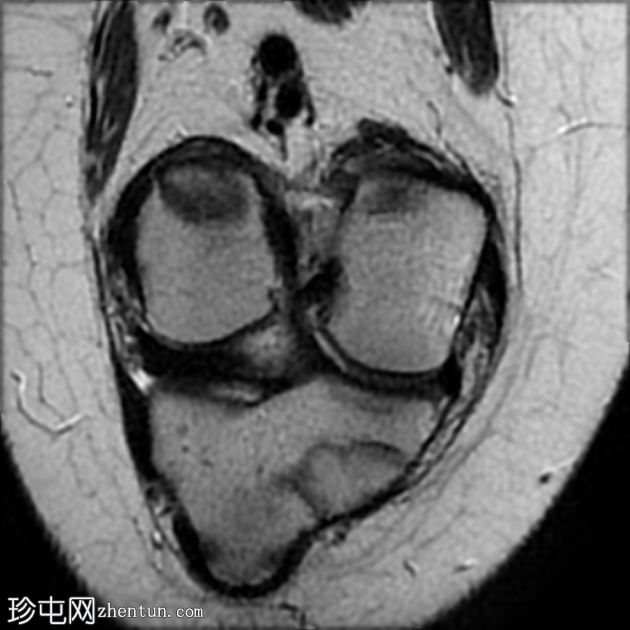

MRI

2.jpeg

矢状位

T2

股骨远端干骺端横向应力骨折线,在所有脉冲序列(T1、T2和STIR)上均呈低信号。其周围有骨髓水肿样信号。邻近骨膜软组织呈水肿样信号。

外侧半月板飞边。

髌腱止点增厚,信号增强,内侧有小部分撕裂。伴有胫骨结节突出和不规则,可能提示慢性Osgood-Schlatter病。

股骨干应力性损伤常见于中长跑运动员和新兵。

最初针对胫骨应力性损伤提出的MRI分级方案:

1级:骨膜水肿,无骨髓改变

2级:脂肪饱和T2加权像上可见骨髓水肿样信号

3级:T1加权像上也清晰可见骨髓水肿样信号

4级:T1和/或T2加权像上可见骨折线